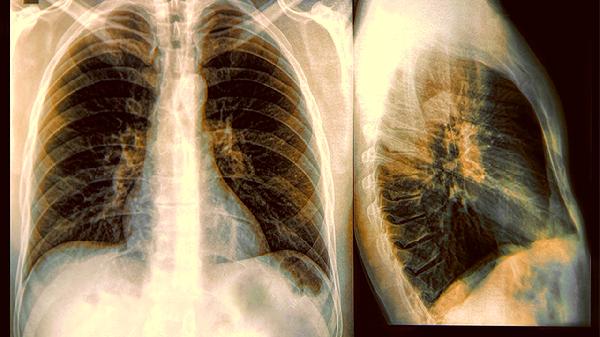

現在的胸腔鏡手術只需要在肋間開幾個鑰匙孔大小的切口,高清攝像頭能把肺部組織放大20倍顯示在螢幕上。主刀醫生操作著細長的手術器械,就像玩體感遊戲一樣精准切除病變,術後留下的疤痕比指甲蓋還小。

借助三維重建技術,醫生能提前在電腦上模擬手術路徑。有些醫院還會用CT引導下的染色定位,給結節標記上”螢光記號””,確保手術時能快速鎖定目標,避免在肺組織裏”大海撈針”。